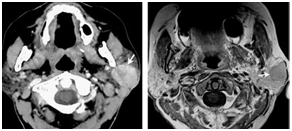

These are differentiated from nasopharyngeal carcinoma by endoscopy and CT scan with intravenous contrast (Figure 7).5

Figure 7 Axial contrast enhanced CT, and axial gadolinium enhanced T1 weighted imaging of malignant salivary gland tumor.5